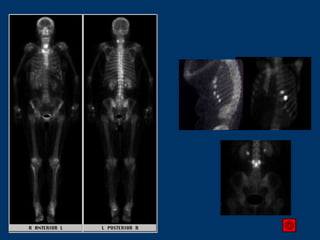

< 5% das cintilografias são normais em pacientes com lesões vistas no RX 10-40% dos pacientes com metástases ósseas têm RX normal e cintilografia alterada Em 30% dos pacientes com tumor conhecido se apresentando com dor e RX normal a cintilografia óssea mostra lesões metastáticas O RX é pouco sensível, e pode demorar 6 meses para evidenciar resposta, além de ser difícil avaliar a resposta em lesões inicialmente escleróticas. Cintilografia Óssea Cintilografia x RX

Exames bem feitos e com boa qualidade tem alta sensibilidade e especificidade 260 Pacientes 1191 Rastreamentos 10 anos de follow up Sensibilidade: 98,2% Especificidade: 95,2% Acurácia: 95,5% VPP: 72,8% VPN: 99,8% Cintilografia Óssea Interpretação J Nucl Biol Med 1993; 37:57–61

Cintilografia óssea Metástases são mais comuns em pacientes com níveis altos de PSA e tumores pouco diferenciados na biópsia, independente da idade A cintilografia deve ser realizada se o PSA for > 20 ng/ml em pacientes com histologia G1 ou G2, e em pacientes com histologia G3 e doença localmente avançada, independente do PSA A cintilografia óssea não é necessária em pacientes com tumores iniciais, PSA < 20 ng/ml e Gleason <=7, a não ser que haja sintomas sugestivos de metástases Não é necessário realizar cintilografia de rotina no follow-up se não houver mudança nos marcadores séricos ou sintomas sugestivos de metástases A cintilografia óssea deve ser realizada quando há alterações rápidas nos marcadores ou quando há surgimento de quaisquer sintomas